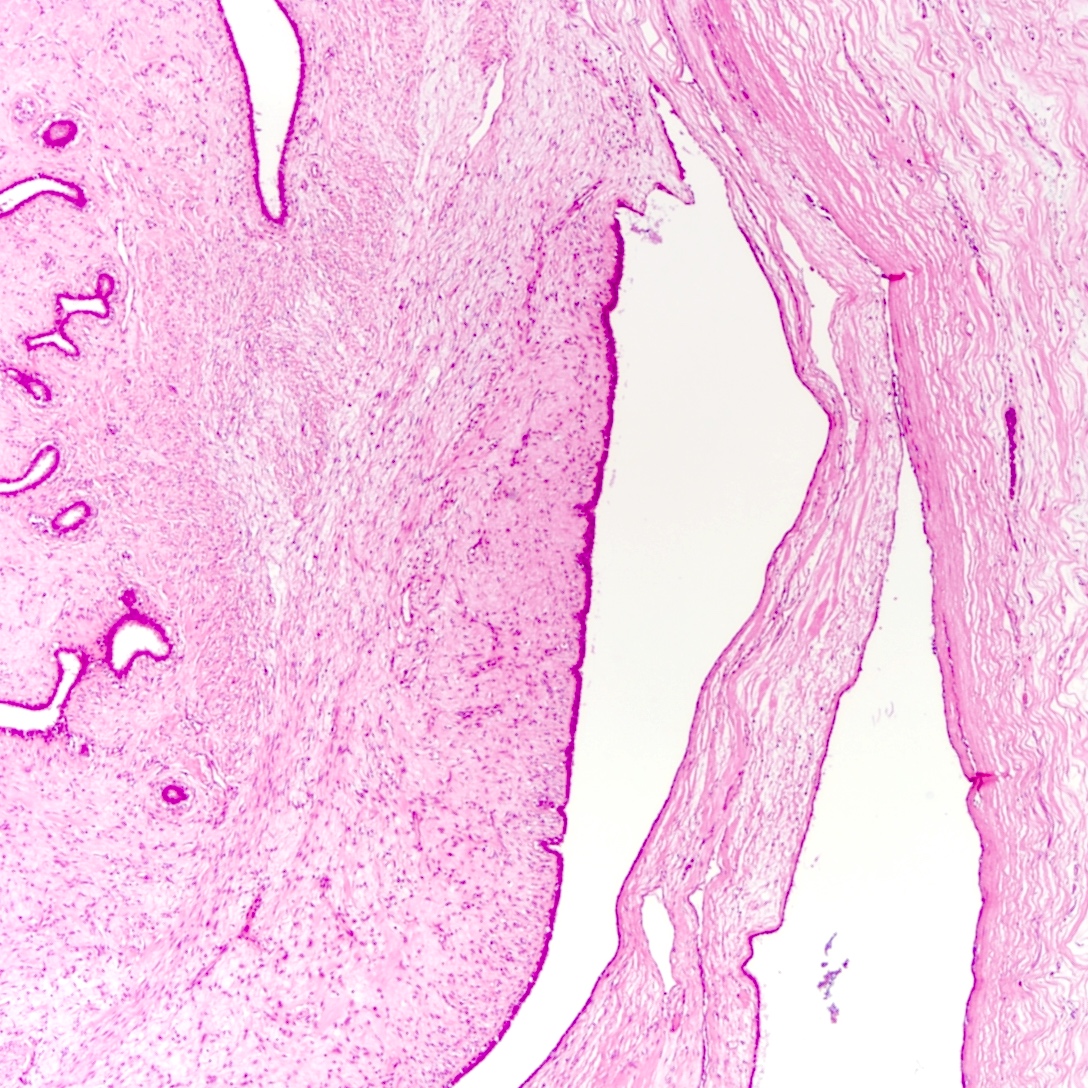

Microscopic (histologic) description

- Leaf-like (phyllodal) epithelial pattern formed by an exaggerated intracanalicular pattern

- Subepithelial condensation with increased stromal cellularity adjacent to epithelium

Microscopic (histologic) images

Contributed by Joshua J.X. Li, M.B.Ch.B. and Gary M. Tse, M.B.B.S.

Benign phyllodes tumor